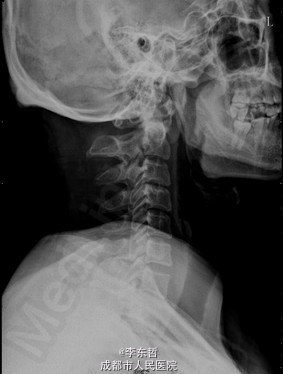

陈旧性寰枢关节脱位

患者男性,54岁,因“外伤后头颈部疼痛2年加重伴活动受限1个月”入院,自诉疼痛呈慢性起病,间歇性、反复发作并逐渐加重,为求进一步诊治故来我院,门诊以“陈旧性寰枢关节脱位”收入我科。